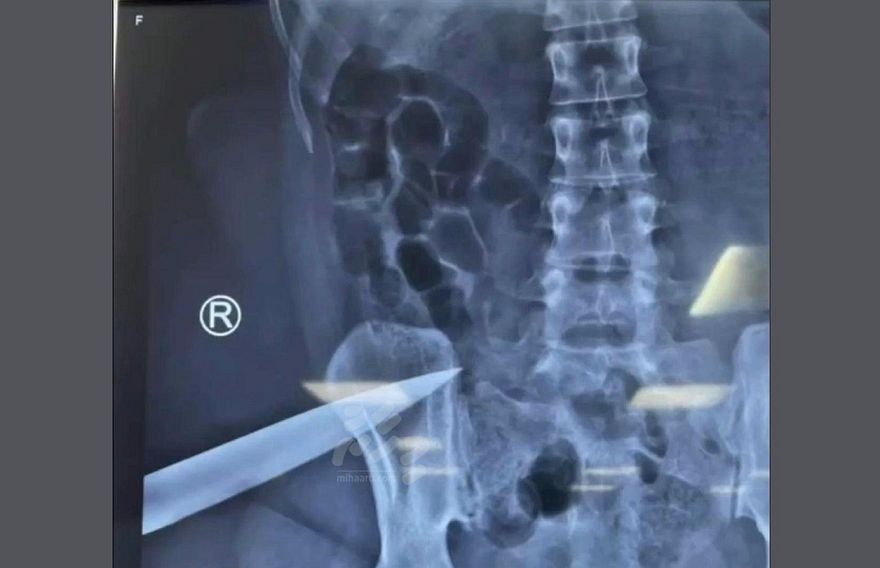

އެ ދައުވާގައި ބުނާ ގޮތުން ސްރިނިވަސަން އޭނާގެ އަނބިމީހާގެ ފައިގެ ފަލަމަސްގަނޑަށް ވަޅި ހެރީ ސިޓިން ރޫމުގައި ނިދާފައި އޮއްވަ އެވެ.

އަންހެންމީހާ ހޮސްޕިޓަލަށް ގެންދިޔައީ ވެސް އޭނާގެ ފޫކޮޅުގެ މަސްގަނޑާ ދިމާލަށް ހަރާފައިވާ ވަޅިއާ އެކު، ވަޅި ނުނައްޓަ އެވެ. އޭނާ ހޮސްޕިޓަލަށް ގެންދިޔަ މަންޒަަރު ފެންނަ ވީޑިއޯއެއް އާންމުވި އިރު އަންހެން މީހާގެ ހެދުމުގެ ތިރި ލެއިން އޮތީ ތަތްތެޅިފަ އެވެ. އަދި އޭނާ ރޮއެ، ގިސްލާ އަޑު ވެސް ވީޑިއޯގައި އިވެ އެވެ.